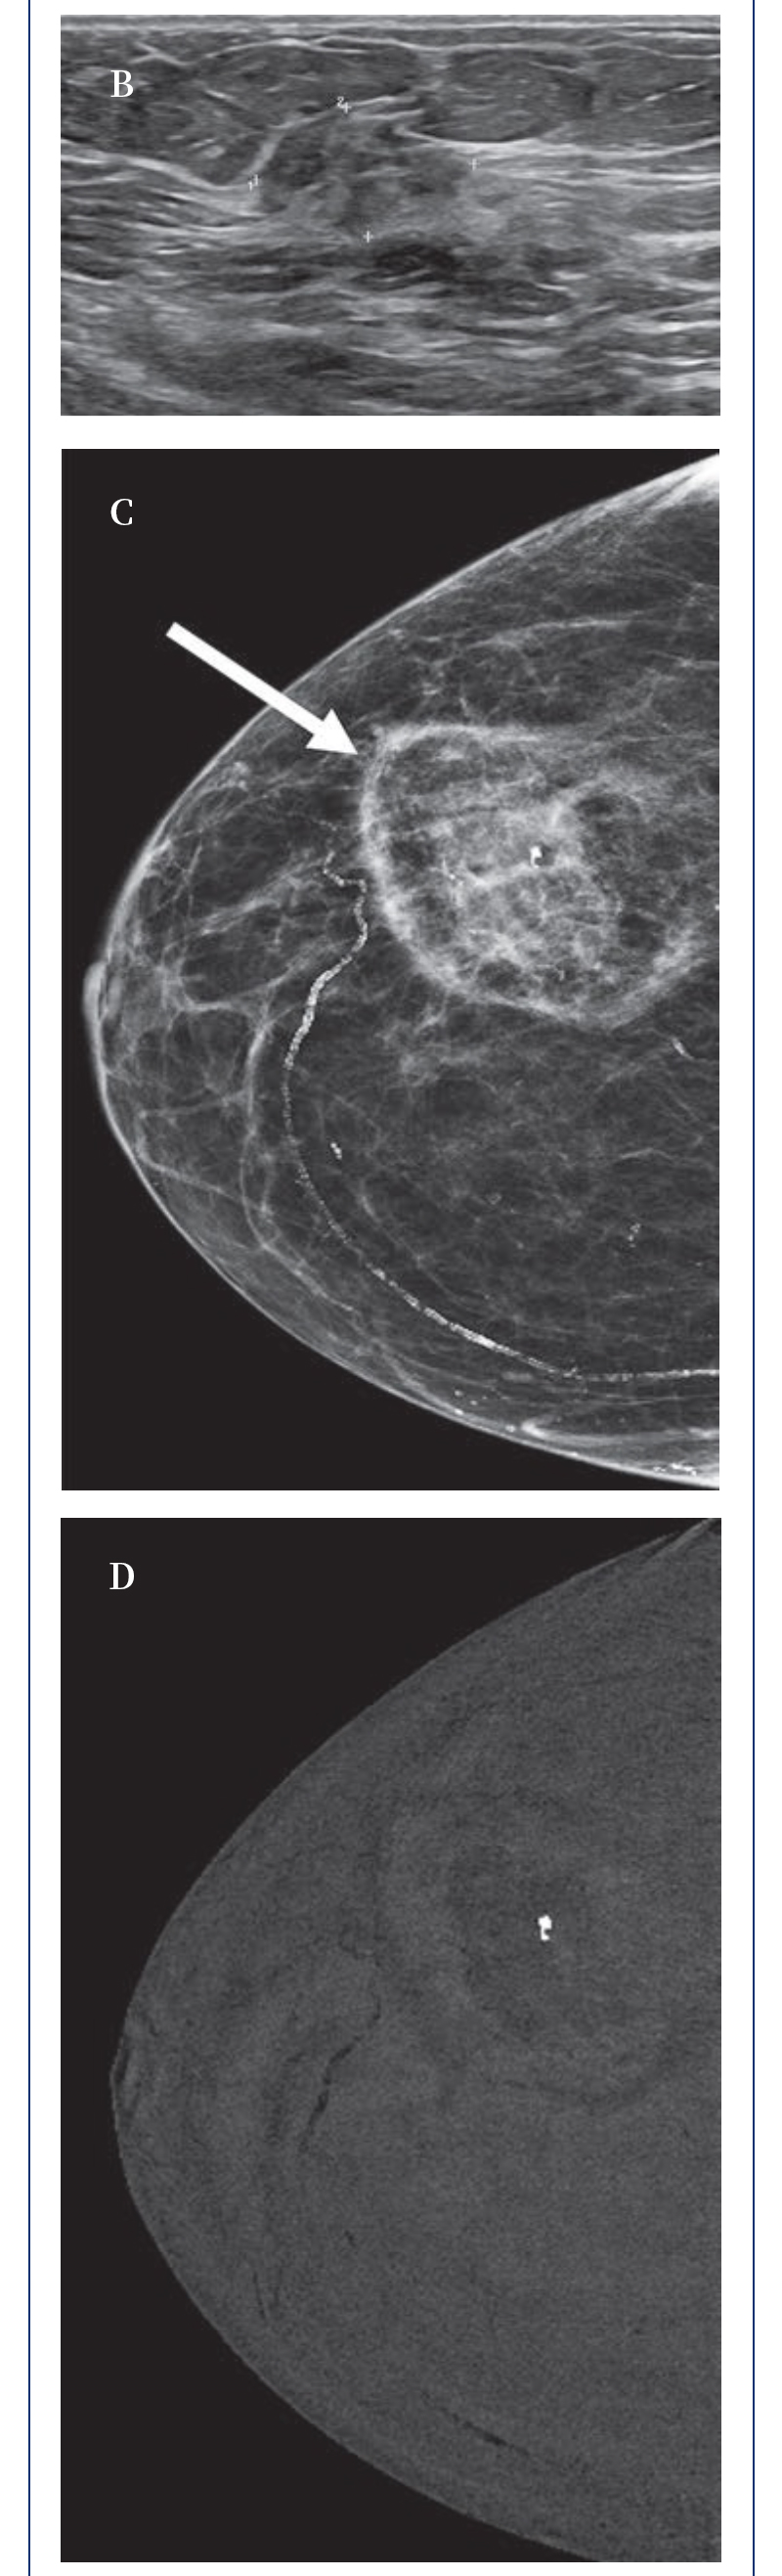

ELF ? 復合式冷熱消融系統(tǒng)